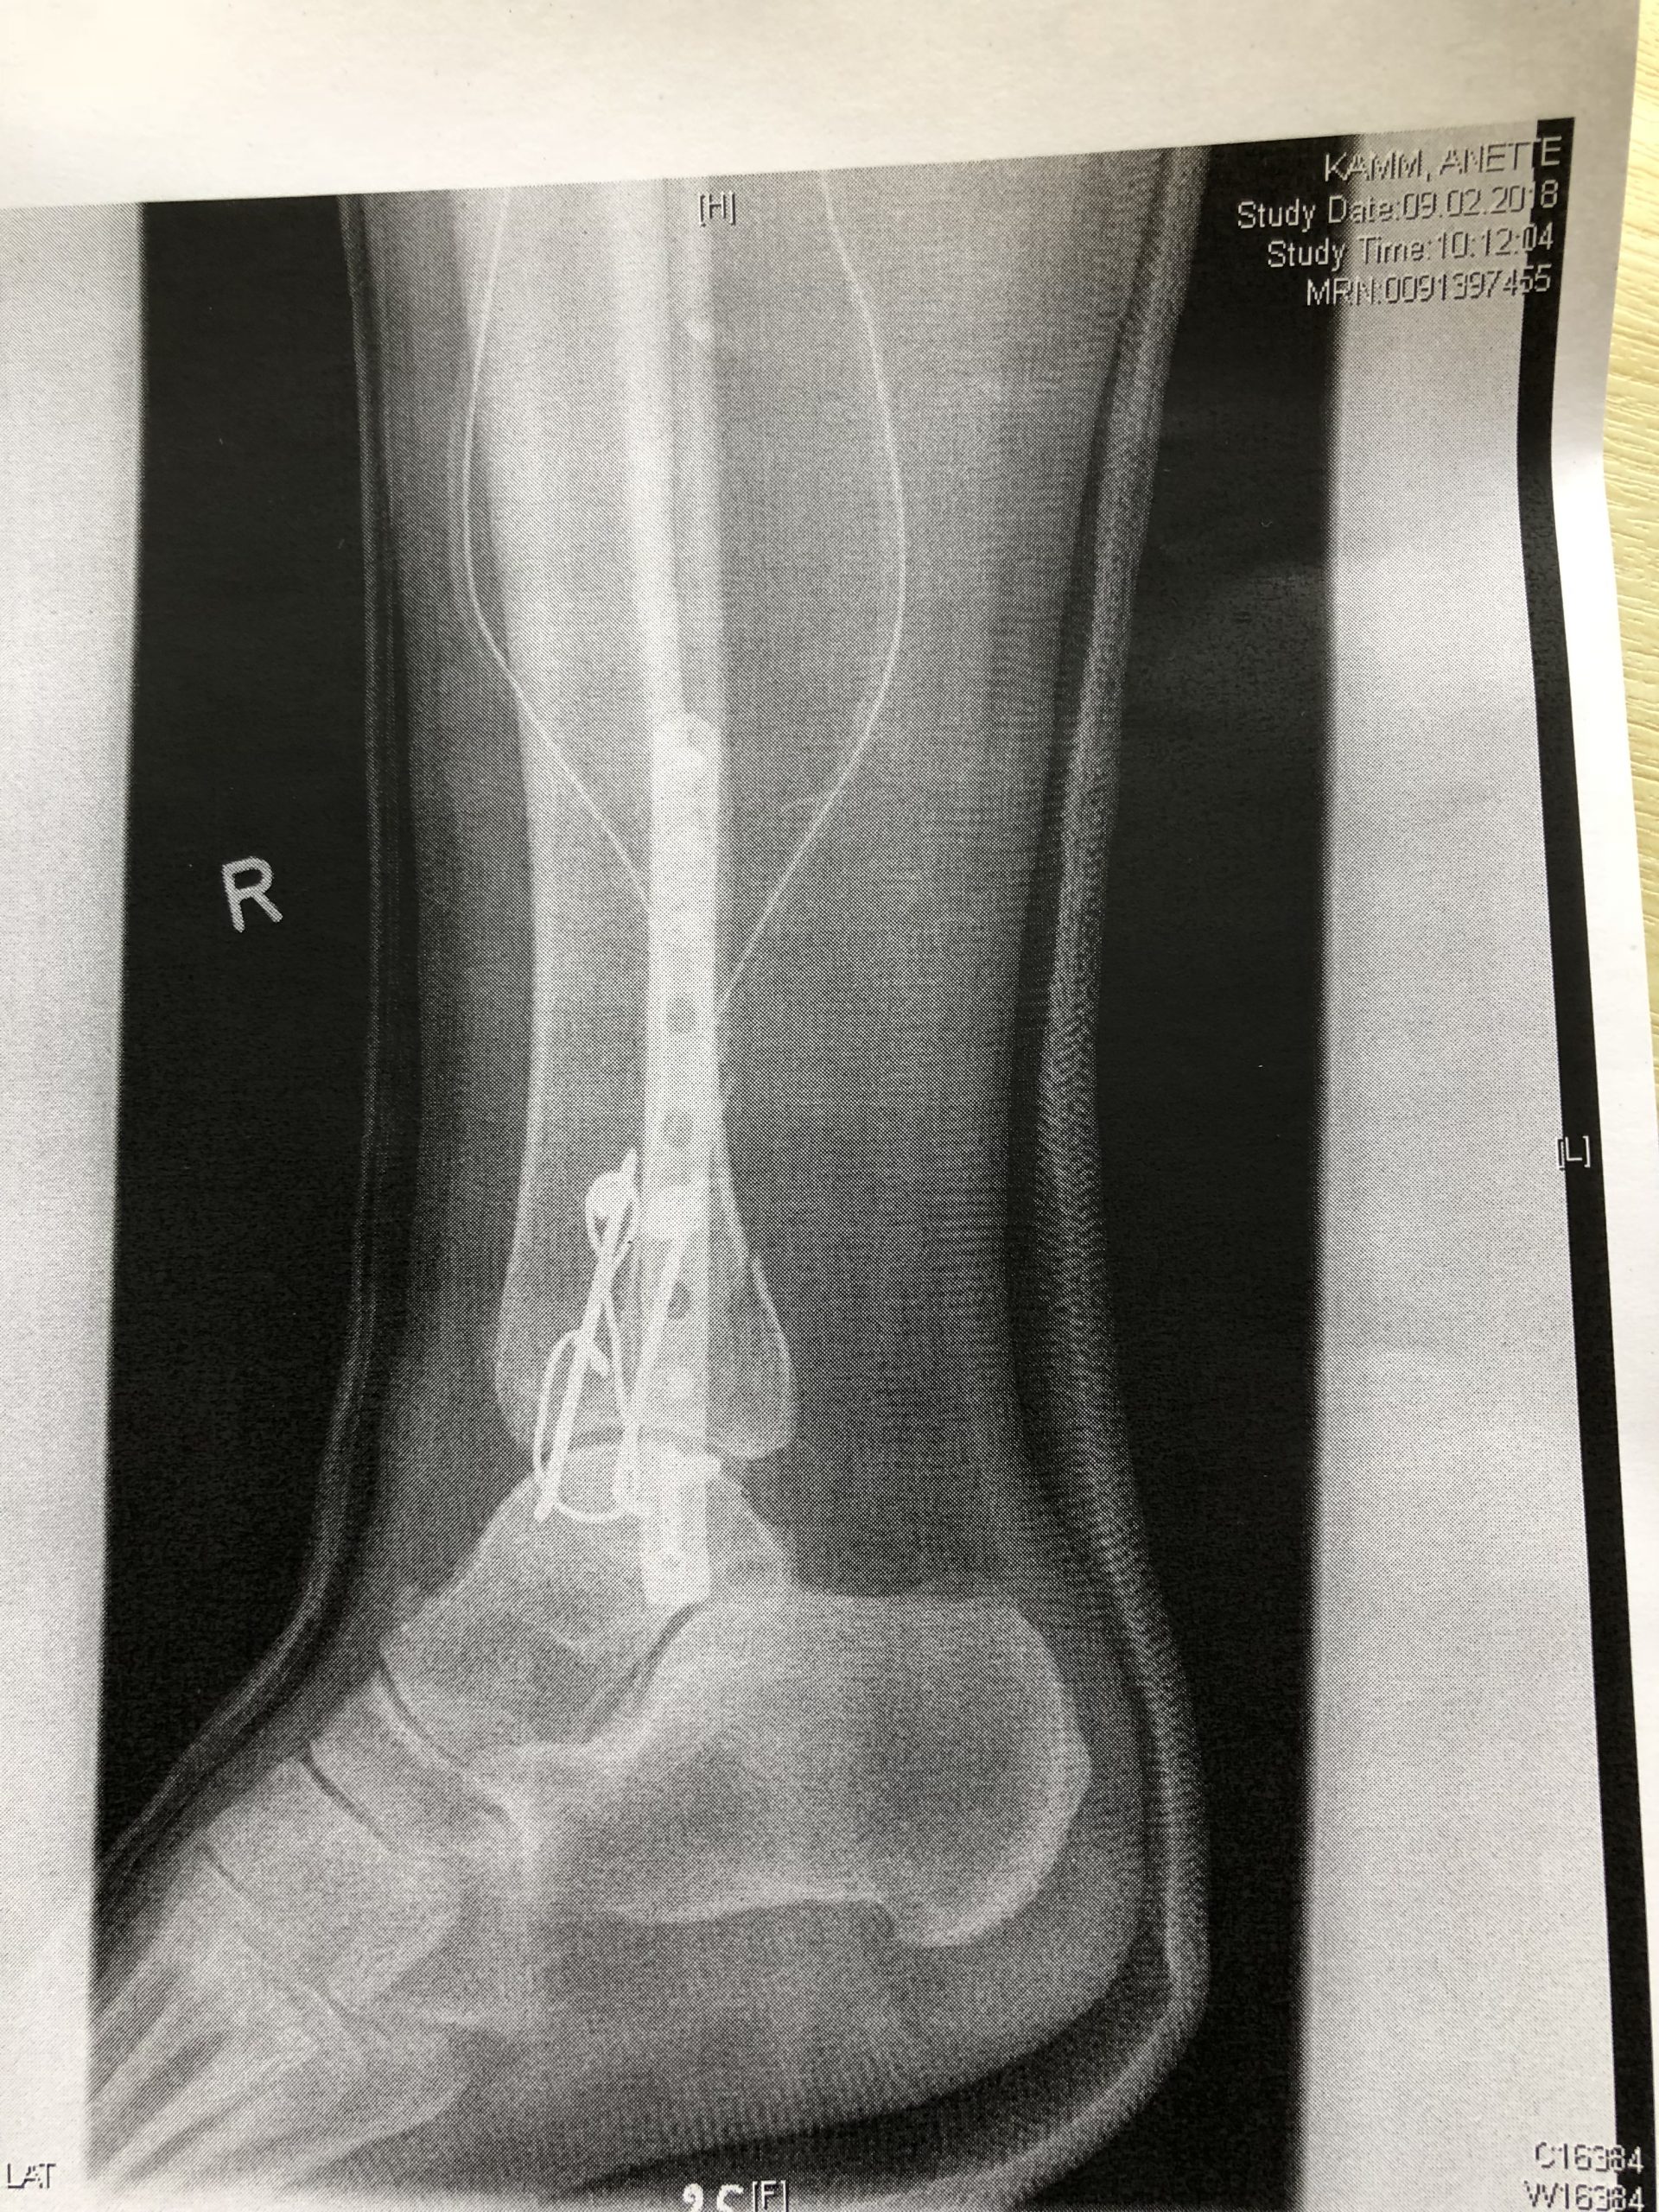

Drähte, Leisten und Schrauben ... was man in so ein Bein alles einbauen kann, damit es wieder richtig zusammen wächst